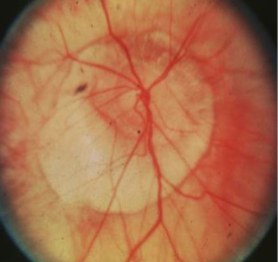

coloboma of ONH

ONH coloboma

etiology: incomplete closure of embryonic choroidal fissure

rare, unilateral or bilateral

appearance:

inferior portion of ONH affected w/ significant excavation & pigment hyperplasia

white bowl-shaped excavation

depth of excavation varies

larger appearing ONH w/ unusual vascular pattern

associations:

coloboma of choroid/retina, lens, iris

complications:

variable VA: normal to NLP

associated VF defects

strabismus

micro-ophthalmos

RD

NTG confusion

must r/o systemic abnormalities

coloboma, heart defects, atresia of nasal choanae, retarded growth & development, genital &/or urinary anomalies, ear anomalies & sensorineural hearing loss

what is CHARGE syndrome?